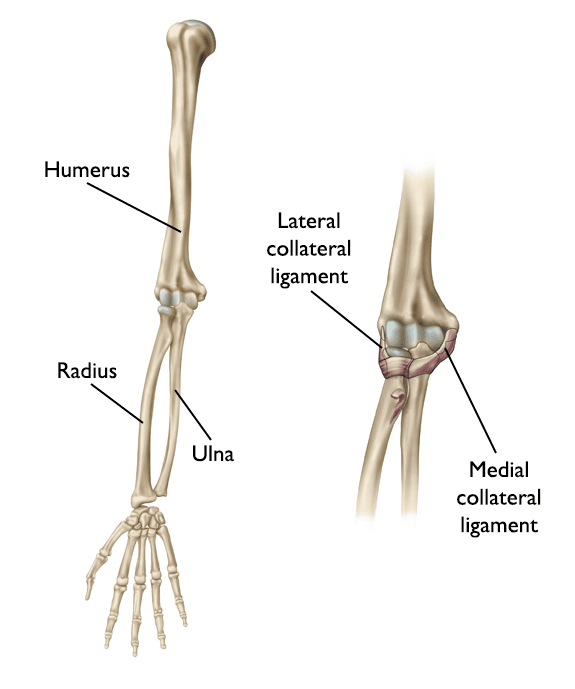

• Varus posteromedial rotatory instability. The elbow slides in and out of the joint due to an injury of the lateral collateral ligament complex, in addition to a fracture of the coronoid portion of the ulna bone on the inside of the elbow.

elbow fracture and dislocation

A fracture of the coronoid process and a dislocation may lead to an unstable elbow that requires surgery.